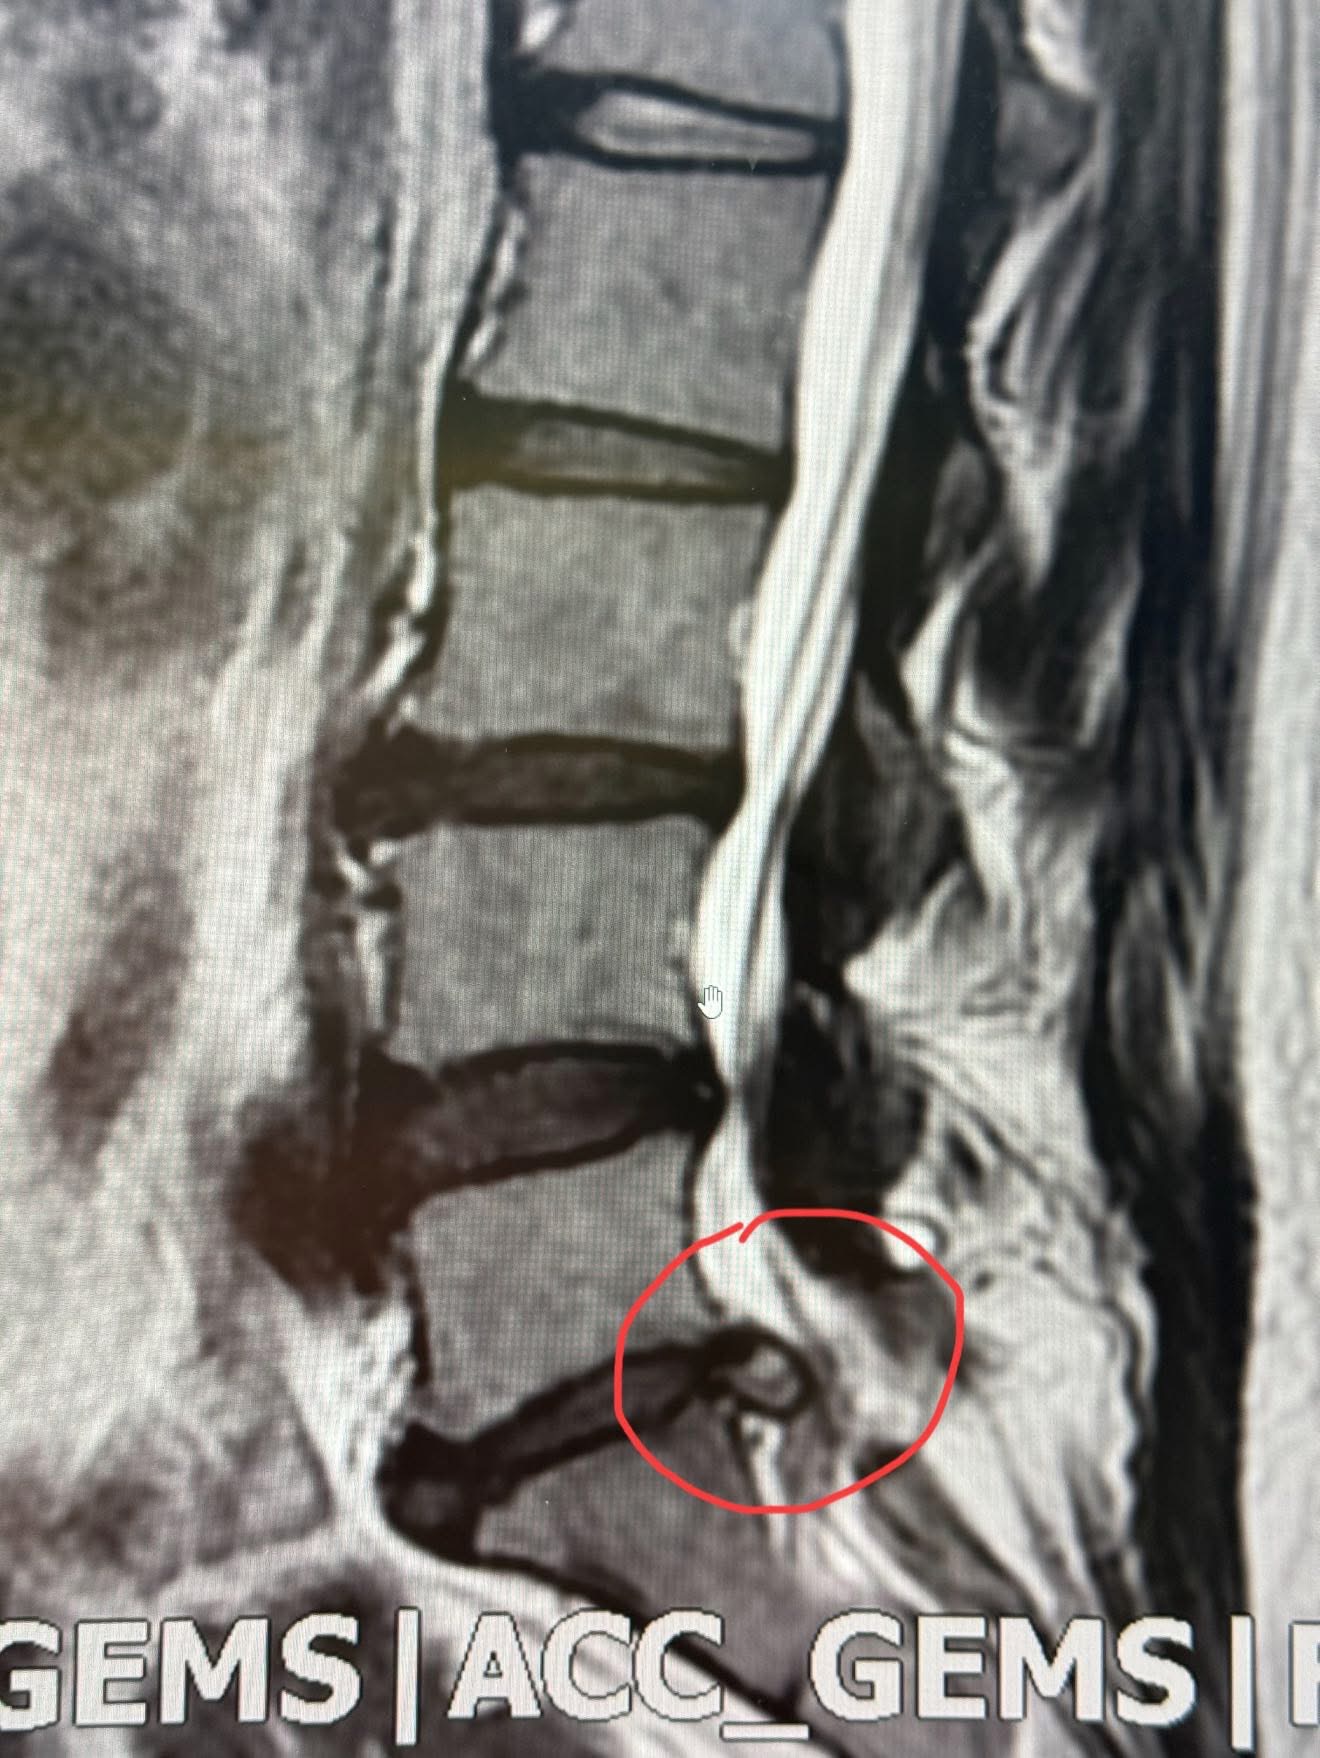

Cervical Spine Treatment Cases 腰椎治療案例 美國開腰椎手術要兩百萬?VS 台灣三週針刀療程的奇蹟 2025.09.23 五年之內歷經三次脊椎大刀之後的醫療反思。 下背手術失敗綜合症候群的一些觀點 脊椎微... 2025.09.22 「脊椎手術有它的價值,但不是每個人都需要大刀──針刀療法給病人多一個選擇」 📌 脊... 2025.09.18 #巨大椎間盤突出一定要開刀嗎? #三家醫院骨科醫師說很嚴重需要手術 #難道真的沒有第... 2025.09.17 ⭕️巨大椎間盤突出,PRP治療失敗、痛到掰咖…他差點走上手術台,卻在這裡看見奇蹟 ⭕️醫... 2025.09.07 【少棒奪冠、脊椎隱憂與台灣棒球的困境】🇹🇼⚾️ 「睽違29 年後的淚水,背後卻有個殘酷... 2025.08.25 ✈️【一張差點被腰痛奪走的法國機票】 ✅一張飛往法國的機票,因為「腰椎管狹窄」而延宕... 2025.08.21 《一碗528元米其林等級牛肉麵的代價》 《脊椎椎間盤巨大脫垂破裂醫案》 「請問還有哪... 2025.08.20 ▶️老人腰痛的真相:骨頭不是第一個壞掉的。 ‼️腰不在骨,根在腸。養脾胃,就是養肌肉... 2025.08.18 【脊椎手術後,還能做針刀嗎?】—— 從筋膜談起的重要四個問題 文/脊椎針刀專門醫... 【足底筋膜痛,竟來自腰椎——多年的疼痛故事】 ✅不是每一個足底痛,都是足底筋膜炎 ... #腰痛別輕忽 #不一定要開刀 #看懂筋膜的語言 #年輕人的腰痛也要重視 #身體健康逆轉勝... 【再次脊椎手術之前,請你聽我說——花蓮陳阿姨的故事】 文/脊椎針刀專門醫師,台灣... 2025.07.30 ✅一年痛到暴瘦十幾公斤,竟然靠六次治療翻轉人生?原本說要開刀,最後成功告別手術。 2025.07.22 ⭕️從超痛到超好:林媽媽的八個月腰劇烈疼痛故事,以及「不用開刀的神經減壓」如何逆轉... ← 上一頁 1 2 3 4 5 下一頁 →